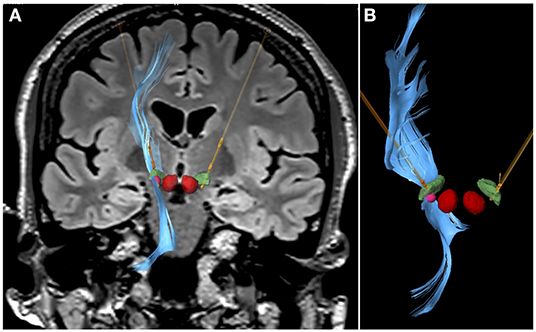

Diagnóstico, manejo de Enfermedad de Parkinson inicial hasta sus fases avanzadas .

Cirugía de Parkinson.

Ultrasonidos en Parkinson ( HIFU )